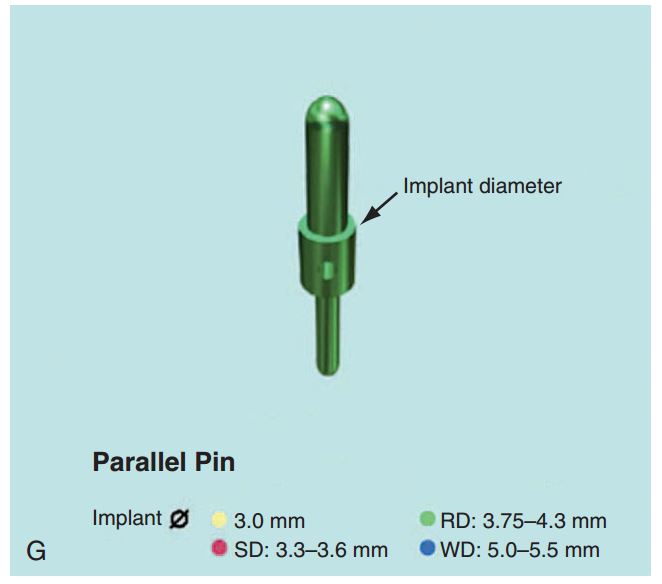

Giúp xác định đúng vị trí đặt Implant và lựa chọn đường kính Implant tối ưu nhất (H2.18). Bộ hướng dẫn ITT gồm có:

– Pin song song, để xác định độ song song của Implant.